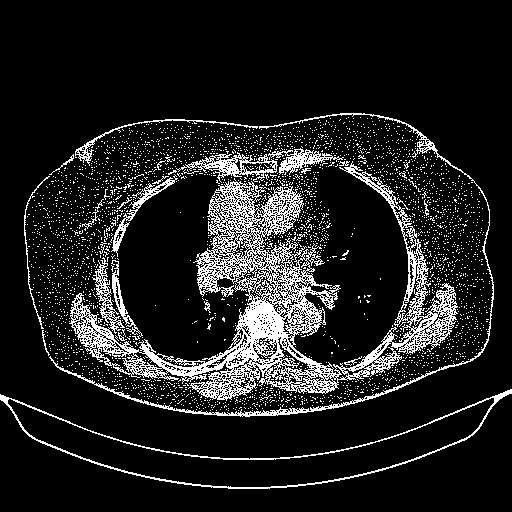

Reconstructed NATIVE CT scan (cycle consistency)

Full window (WL 1023.5, WW 4095 β†’ Low βˆ’1024, High +3071)

Actual HU range: [-1024.0, 3071.0]